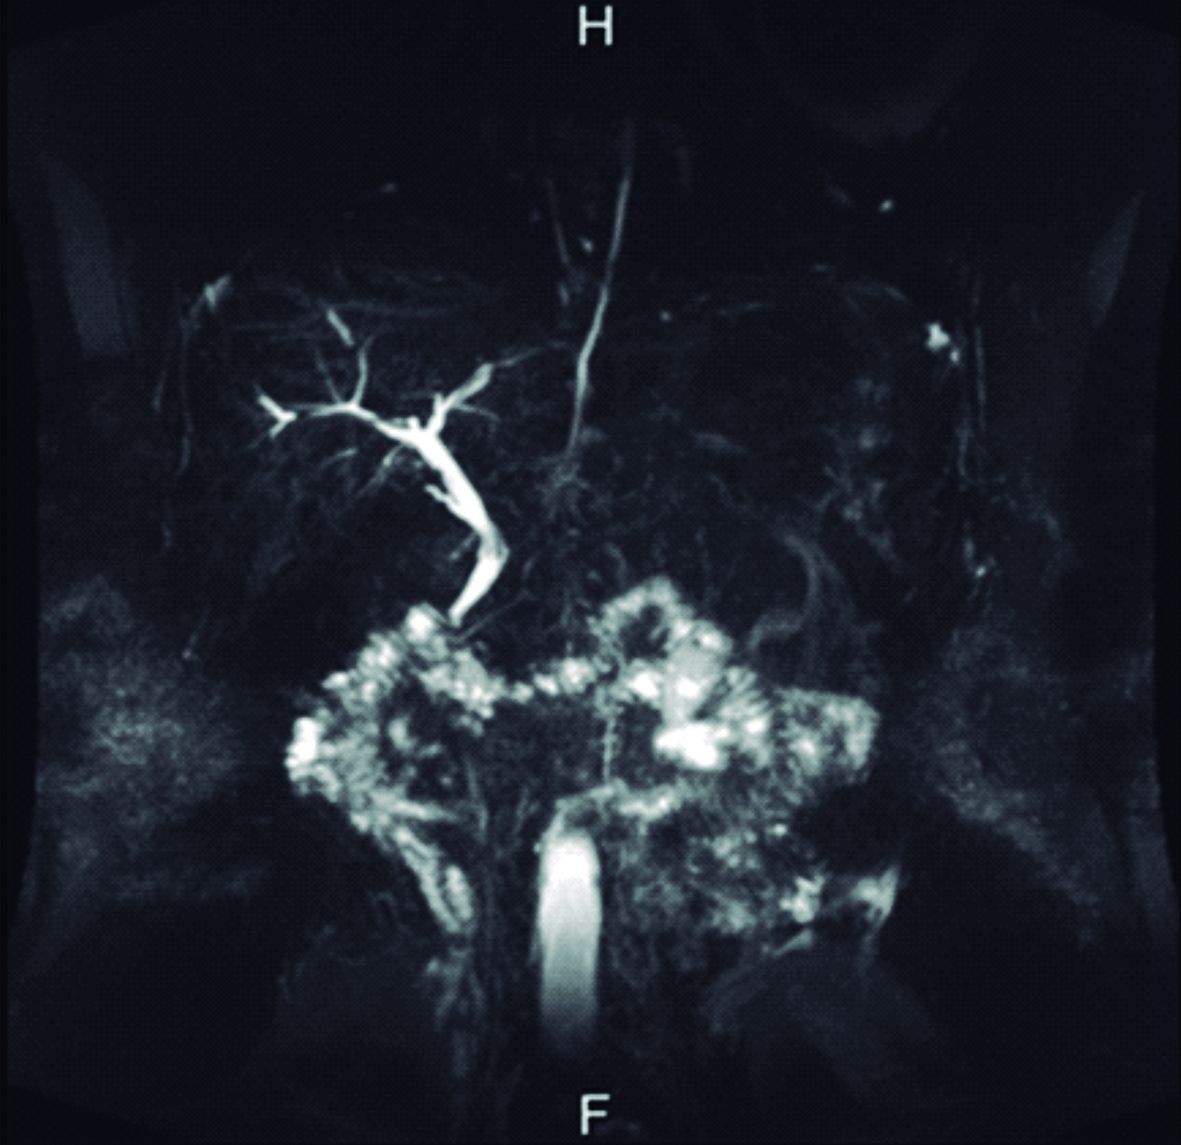

El ultrasonido de abdomen realizado al ingreso mostró vía biliar principal dilatada, a predominio del conducto hepático izquierdo en cuyo interior se observó imagen trilaminar, alargada, sin sombra acústica posterior, compatible con parásito. El extremo cefálico del parásito alcanza el origen de los canalículos de los segmentos póstero-laterales izquierdo y su extremo caudal se extiende dentro de la luz del conducto hepático común y el colédoco. El diámetro mayor del colédoco alcanzó 12mm, el parásito se detectó alcanzando la zona de la papila duodenal, estando plegado sobre sí mismo dentro de la vía biliar principal (Fig. 1).

Figura 1. Ultrasonido en modo B

a) Corte transversal a nivel de epigastrio, en el cual se identifica colédoco dilatado (flecha azul), ocupado por el Ascaris plegado sobre sí mismo (flecha amarilla).

b) Corte longitudinal sobre el colédoco supraduodenal, en el cual se observa el Ascaris plegado sobre sí mismo (flechas amarillas) dentro del colédoco dilatado (flecha azul). H: Lóbulo hepático izquierdo, E: Corte transversal del antro gástrico, VP: Vena porta.